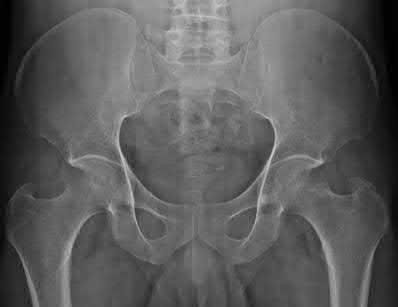

Question 18:

In an anteroposterior compression (APC) type III pelvic ring injury, the symphysis pubis is widely disrupted, and the hemipelvis is completely unstable. Which of the following posterior ligamentous structures is completely disrupted in an APC III injury but intact in an APC II injury?

Correct Answer: Posterior sacroiliac ligaments

Explanation:

APC II injuries involve disruption of the symphysis pubis, anterior sacroiliac ligaments, and the sacrospinous and sacrotuberous ligaments, but the posterior sacroiliac ligaments remain intact (opening book). In APC III, there is complete disruption of the anterior and posterior sacroiliac ligaments, leading to a completely unstable hemipelvis.